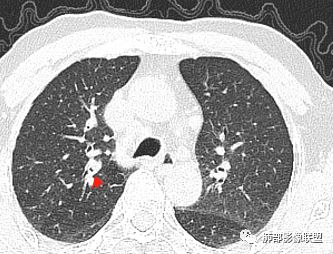

主病灶在中叶,但是左肺舌段叶有条索影,陈旧病变。蓝色箭头支气管受压,是淋巴结肿大

主病灶在中叶,但是还有结节状病变在下叶

边缘还有多发小灶

左下叶背段小结节,舌段索条,内似有扩张支气管

墨西哥仙人掌征---结核        影像上结核灶,粗大的均匀枝干,推测是支气管囊状扩张引起的,在非支气管区,形成圆形坏死囊群;如果这些坏死比较稀薄,又遇到扩张支气管,就会形成粗大的“墨西哥仙人掌”。结核引起的支气管近端炎症纤维化,可以造成支气管阻塞,从而将干酪样坏死物封堵在管腔内。仙人掌主干内部应该是干酪为主,稀薄的,具有流动性,时间久了会出现钙化。

结核坏死与鳞癌鉴别有一点是结核坏死没有方向性,鳞癌有。鳞癌靠近支气管近端部分,血供容易维持,不易坏死,所以坏死靠外侧。而结核干酪样坏死,把一定体积的流动性坏死物,包裹起来,什么形状最省料?坏死物包裹,表面积最省的自然是圆球形,而遇到支气管,坏死物一多,就把支气管撑大了。包裹物是就地取材,扩张的支气管就成了包裹结构。